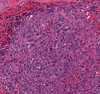

Phyllodes tumor

Biphasic tumor composed of spindled stromal cells and benign epithelial cells. Stromal cellularity is variable, and ranges from paucicellular to hypercellular. Prominent and exaggerated intracanalicular pattern with “leaf-like” projections into variably dilated lumina.

Shown is a malignant phyllodes tumor. The stroma is diffusely hypercellular with pleomorphic cells, mitotic figures, and necrosis. “Stromal overgrowth” (where you can find fields of stroma only) is suggestive of malignancy as well.

Increased incidence in Li Fraumeni syndrome. Presents as a palpable, painless breast mass. Can have heterologous elements that are malignant.

Molecular: MED12 and RARA mutations in benign phyllodes tumors.

TERT promoter, ERBB4, TP53, EGFR, PIK3CA, and RB1 in borderline or malignant phyllodes tumors.